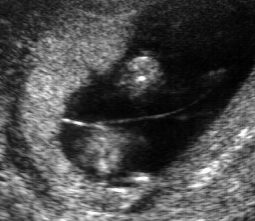

Diagnóstico ultrassonográfico:

- Diagnóstico de espinha bífida requer exame sistemático de cada arco neural, desde a região cervical até sacral, tanto no corte transversal como longitudinal. No corte transverso, o arco neural normal aparece como um círculo fechado com pele íntegra cobrindo, enquanto que nos casos de espinha bífida, o arco tem forma de U e há meningocele abaulada adjacente (cisto de parede fina) ou mielomenigocele. A extensão da lesão e de qualquer cifoescoliose associada é melhor avaliada no corte sagital.

- Localização da espinha bífida aberta: lombossacral (65%), sacral (24%), toracolombar (10%), cervical (1%).

- Espinha bífida aberta é associada à Malformação de Arnold-Chiari II com deslocamento caudal do tronco cerebral (brain stem – BS) e obliteração da cisterna magna.

- Com 11-13 semanas, no corte sagital médio da cabeça, a parte inferior do cérebro entre o osso esfenoide anteriormente e o osso occipital (occipital bone – OB) posteriormente, pode ser dividida em tronco cerebral anteriormente e uma combinação de 4o ventrículo e cisterna magna posteriormente. Na maioria dos casos, o diâmetro do tronco está aumentado, a distância entre o tronco e o osso occipital (“BSOB”) está diminuída e a razão BS/BSOB é >1.0 .

- No segundo trimestre, mais de 95% dos fetos apresentam acavalgamento dos ossos frontais ( sinal do limão) e obliteração da cisterna magna com “ausência” de cerebelo ou curvatura anormal dos hemisférios cerebelares ( sinal da banana). Grau variável de dilatação ventricular está presente em todos os casos de espinha bífida ao nascimento, mas em apenas 70% dos casos no segundo trimestre.